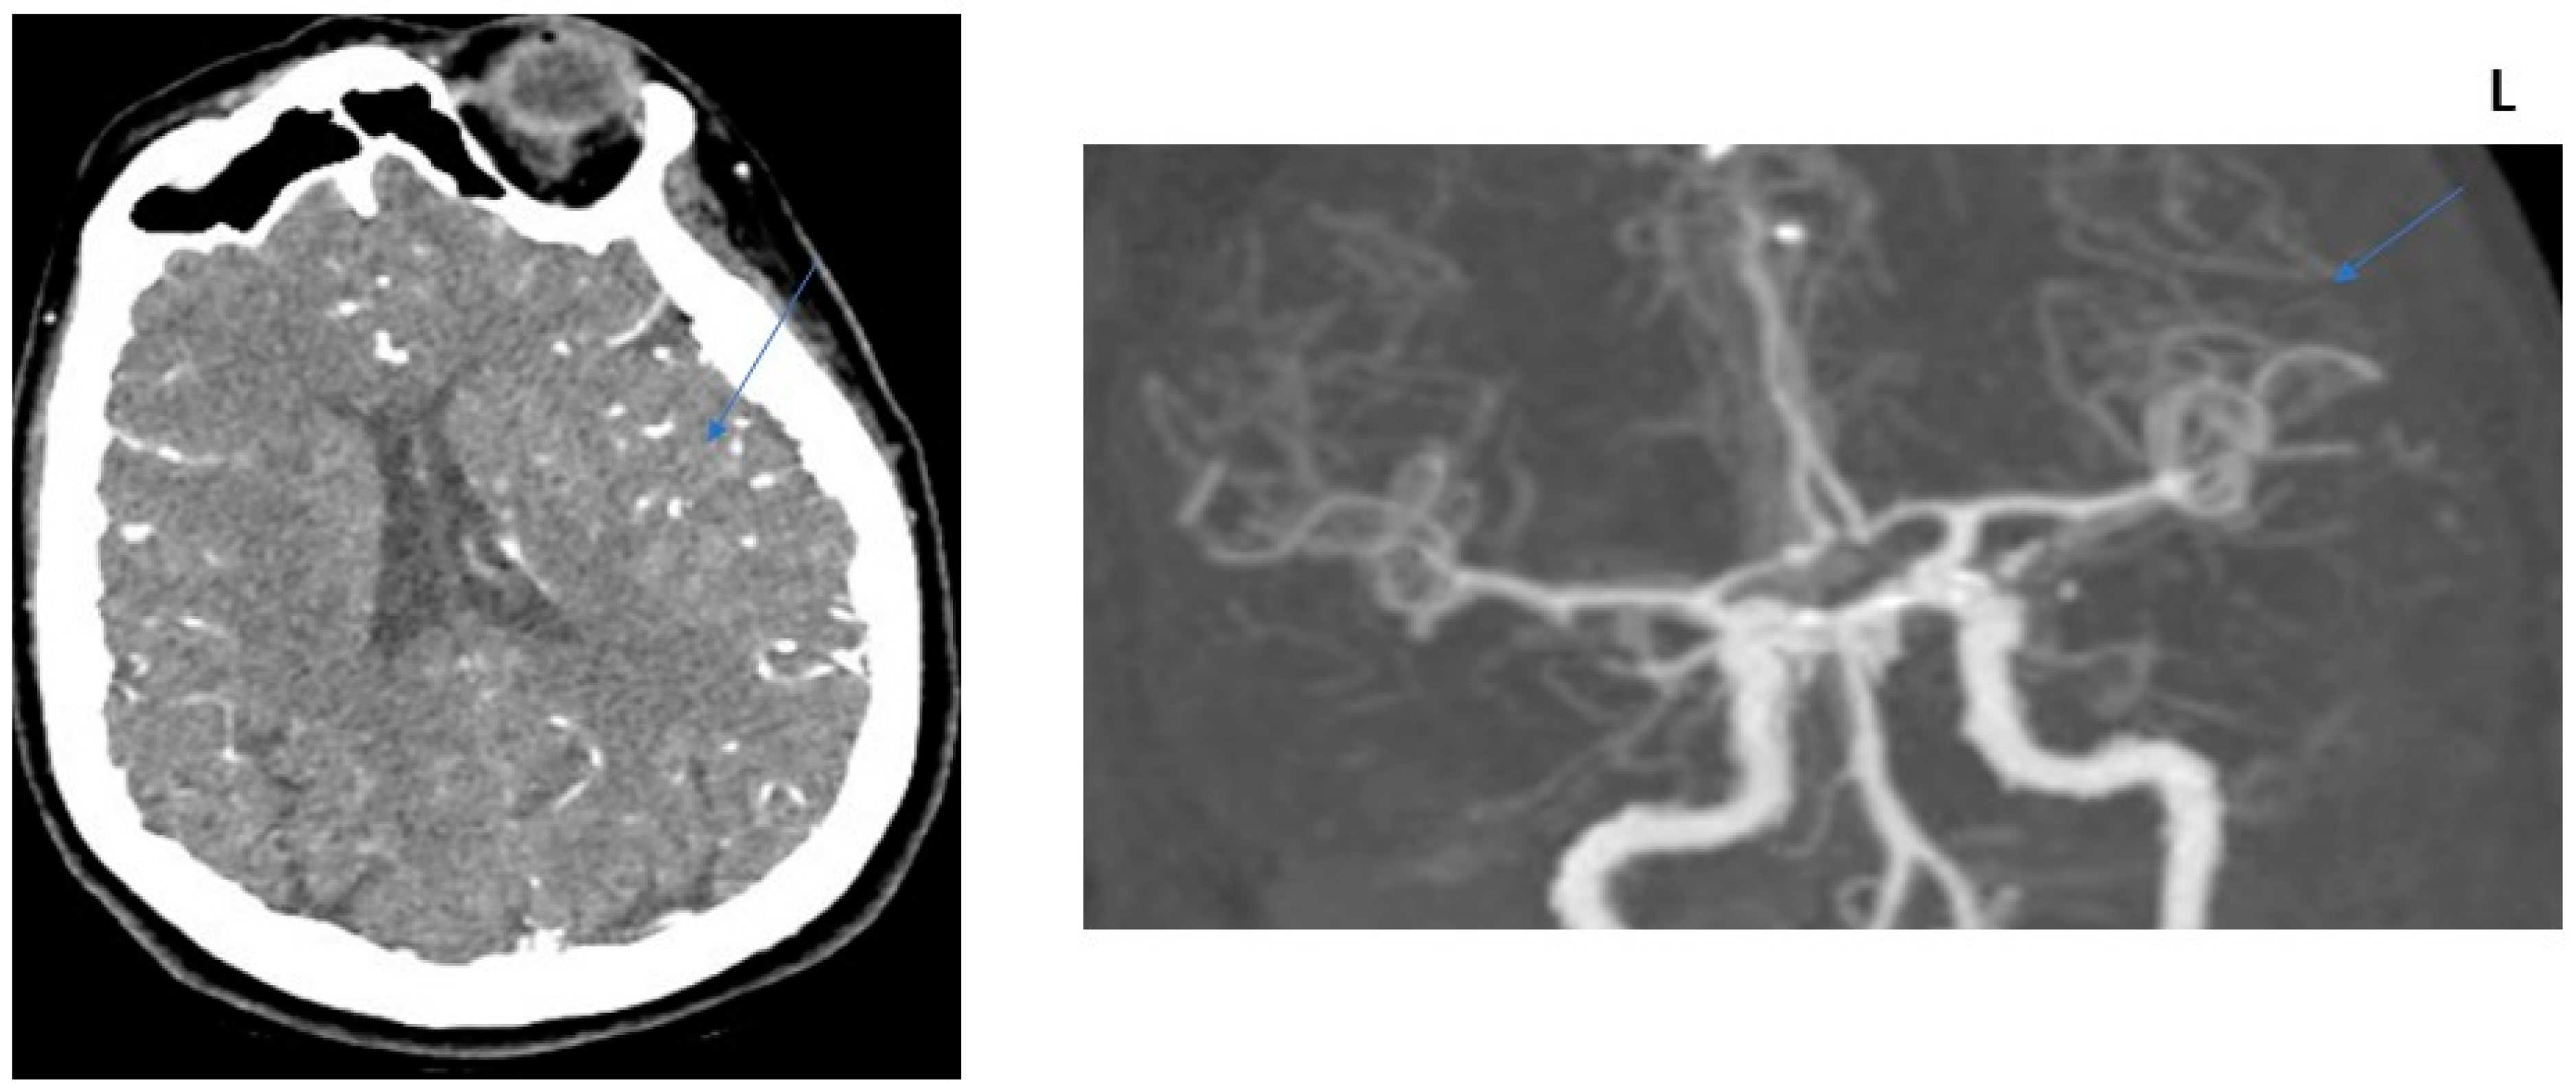

2.2. CT Protocol